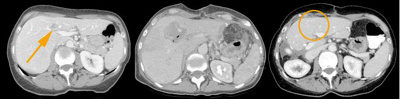

chirurgisches-zentrum-irreversible-elektroporation-bilder-lebermetastasen

Schwierig gelegene Lebermetastase (links), unmittelbar nach der irreversiblen Elektroporation (Mitte) und mit narbenfreier Erholung nach Behandlungsabschluss (rechts).